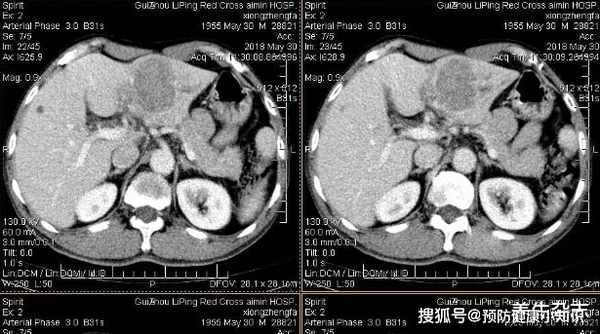

到了醫院後,醫生聽聞王羽近來嗜睡的狀態,又發現他眼白發黃,建議他立即做一下肝CT等相關肝功檢查。

經過多種醫療檢查後,發現王羽甲胎蛋白高達480,確診肝癌晚期,且癌細胞已擴散。